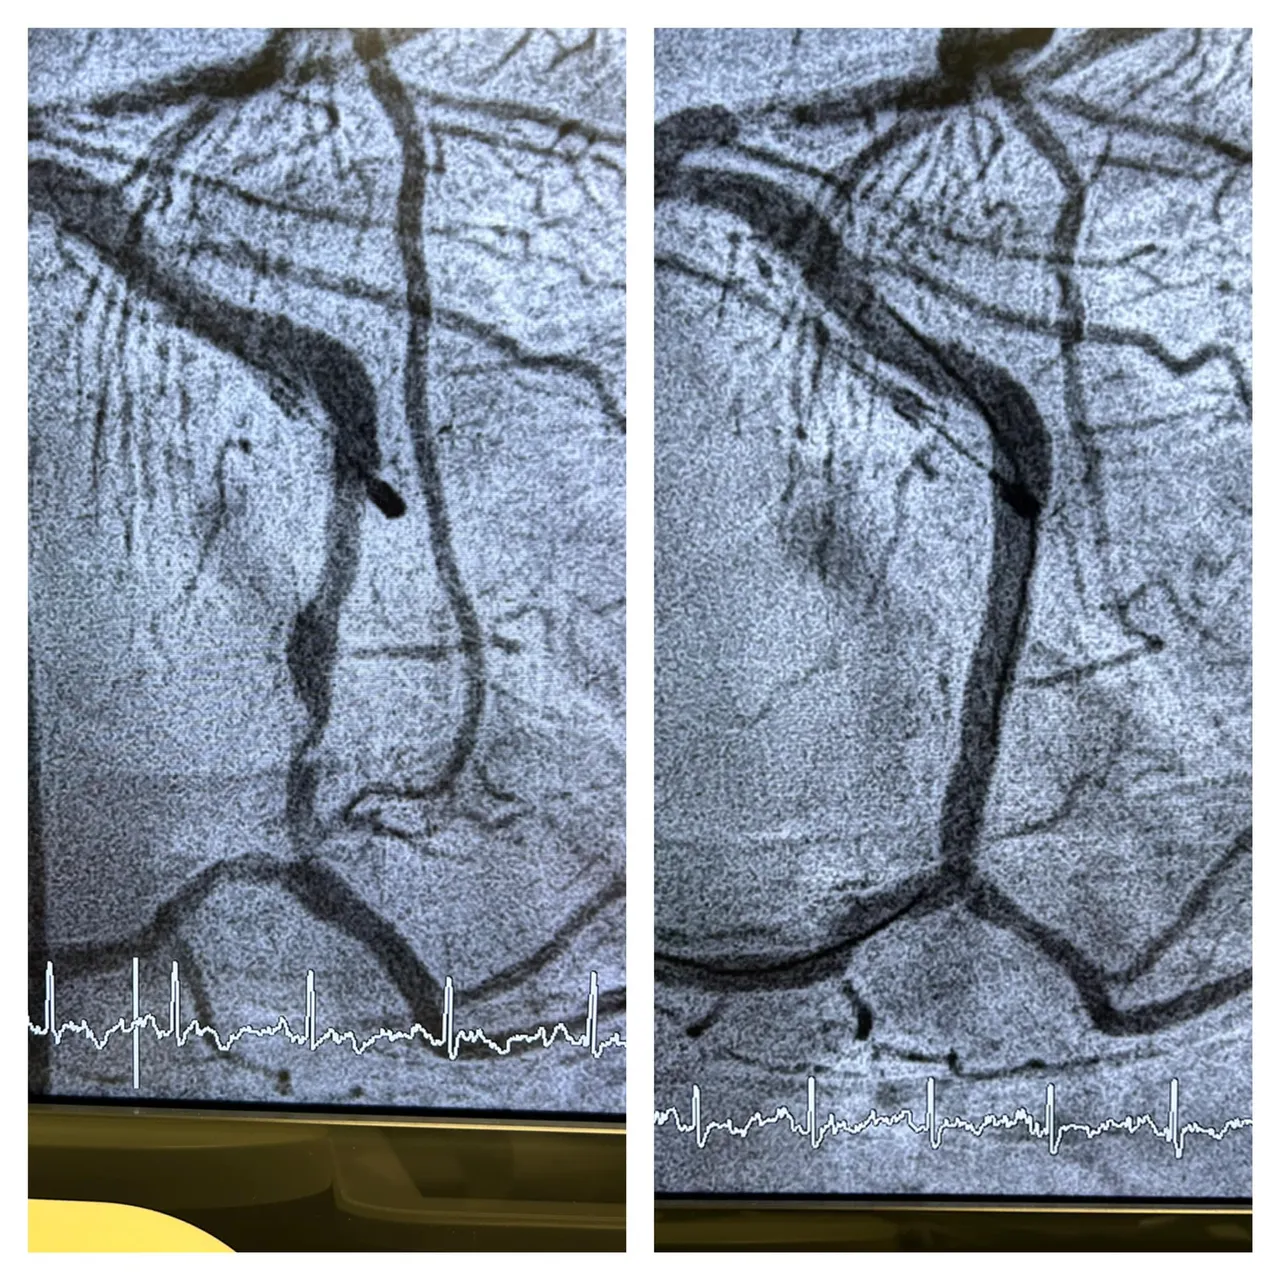

「不做不知道,一做吓一跳」陈冠任说,她的心电图竟然呈现急性心肌梗塞,必须立即做紧急心导管手术,告知道若不马上打通心脏血管,会有生命危险,要她马上联络小孩,立刻来医院。

陈冠任表示,术后发现大姐有两条血管狭窄超过九成以上,不处理随时会有猝死的可能,幸好手术顺利目前两条都已畅通,人的症状也改善许多。他表示,该患者术后仍要乖乖控制高到爆表的坏胆固醇,不然根源问题未除,血管病变还是会反复发生的,不是每次都能像这次这么幸运。